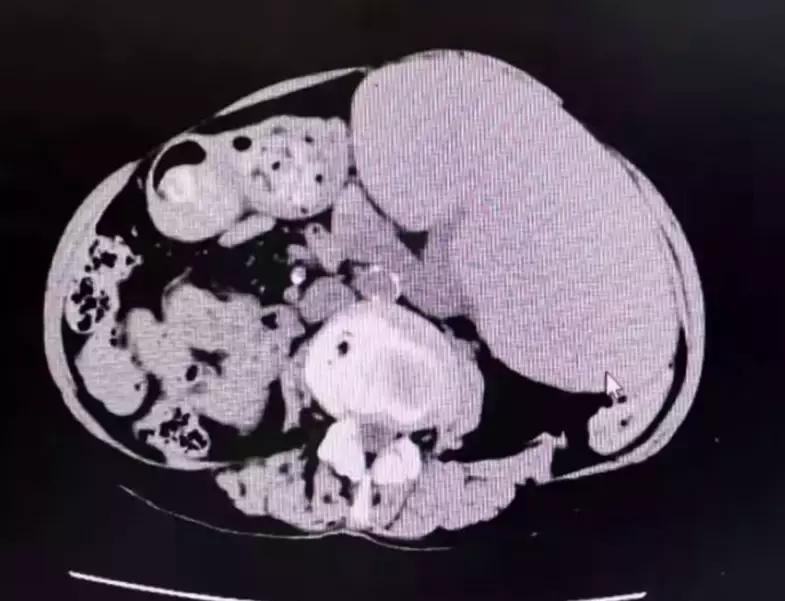

做腹部CT发现这个患者脾脏巨大,属于巨脾症,会导致重度贫血。之后做了一个手术,手术很成功,患者的营养状况已经有所改善,饮食饭量也增加了。目前,周奶奶仍在医院观察治疗中。